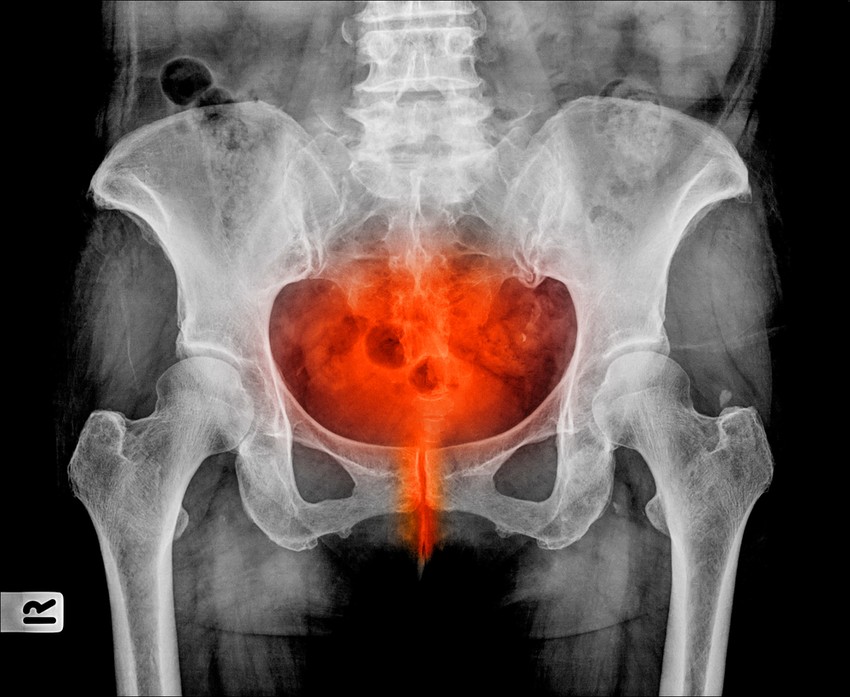

Húgyúti fertőzés: a veséje bánhatja, ha az elején nem kezeli

A kezeletlen húgyúti fertőzésből komoly baj is lehet, mutatjuk, mit tehet ellene!

A légúti fertőzések mellett a leggyakrabban előforduló, elsősorban bakteriális eredetű fertőző betegség-csoport, a kórokozók általában másik szervből jutnak át a húgyutakba, és nem ritkán szövődményekkel (pl. vesekő, neurogén hólyag, katéterviselés, cukorbetegség) is járnak.

A húgyúti fertőzések (UTI =urinary tract infection) keletkezésekor az is döntő, hogy fennáll-e bármely mechanikus akadály, működési elváltozás, vagy immunrendszeri, vagy anyagcsere-eredetű eltérés, ami gátolhatja a normális vizelet-elfolyást.